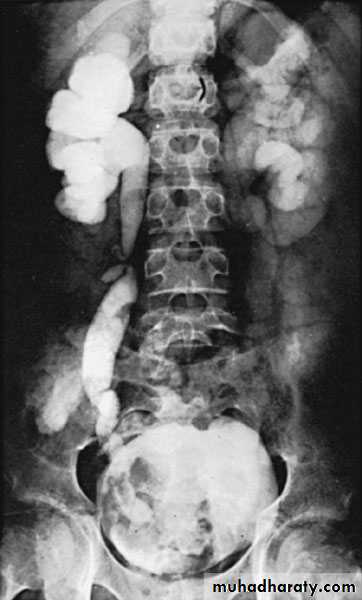

Congenital Megaureter

Grossly dilated ureterUnilateral or bilateral

More common in male

Diagnosis : IVU